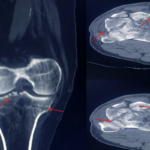

Artificial Human Lumbar Spine Model On The Table With Display Mo